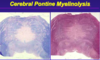

What is PML?

Progressive multifocal leukoencephalopathy = severe demyelinating CNS disease caused by reactivation of the JC virus

What can cause PML?

Duationof treatment w/ natalizumab (monoclonal anitbody for MS)